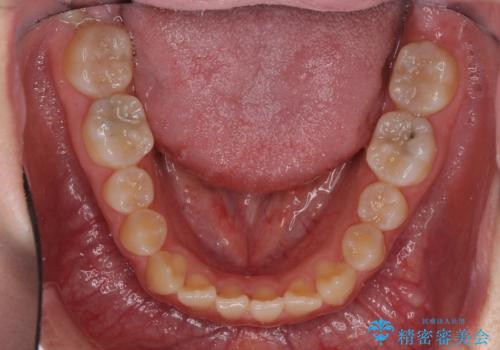

受け口で開咬を急速拡大装置とインビザラインで改善 欠損部分はインプラントにて補綴治療

- 前歯の開咬と、受け口による咬み合わせの悪さを気にして来院された患者様です。

上顎歯列が狭窄していたため、急速拡大装置により上顎骨を側方に拡大し、その後インビザラインにて矯正治療を行うこととしました。